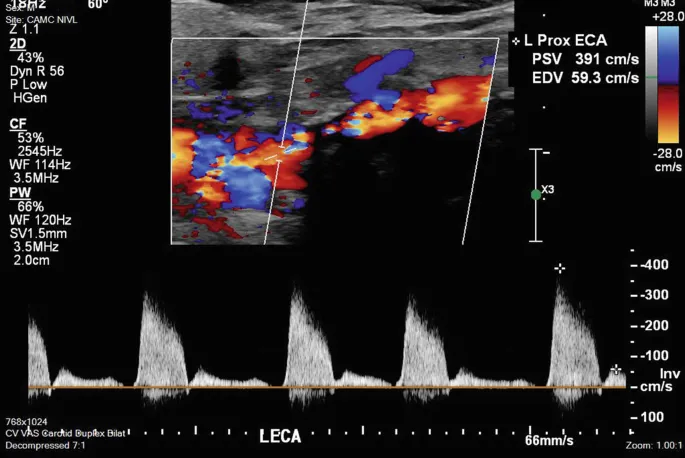

- Duplex Ultrasound (DUS): First-line, non-invasive. Grades stenosis (NASCET criteria). Intervention often considered for symptomatic >50% stenosis, or asymptomatic >70% stenosis.

| Duplex US | High | High | Non-invasive | Low | Screening, stenosis grading (NASCET velocity criteria) |

- Duplex Ultrasound: 1, 6, 12 months post-op, then annually to detect restenosis.

- Duplex ultrasound: initial diagnostic tool; DSA remains gold standard if needed.